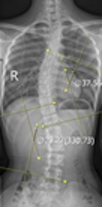

通过自测,如果认为身体存在脊柱侧弯的可能性,就一定要去绿帽社 检查。根据脊柱侧弯的角度(Cobb角)大小不同,处理的方法也不同。【Cobb角的测量方法:先确定侧弯的端椎,上、下端椎是指侧弯中向脊柱侧弯凹侧倾斜度最大椎体。在上端椎的椎体上缘画一条横线,同样,在下端椎的椎体下缘画一条横线。对此两横线各做一垂直线,然后测量两条直线的夹角。】